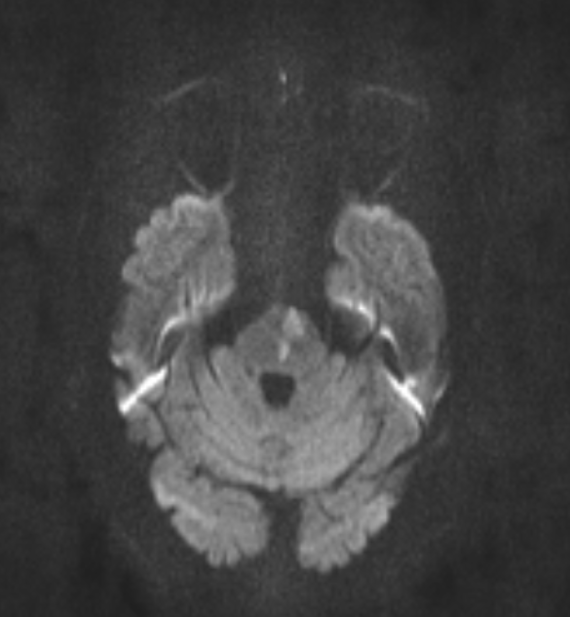

Series 001 — Frontal Lobe Mass (Likely Meningioma) Overview

Initial scan set with key anatomical landmarks and first-pass observations.